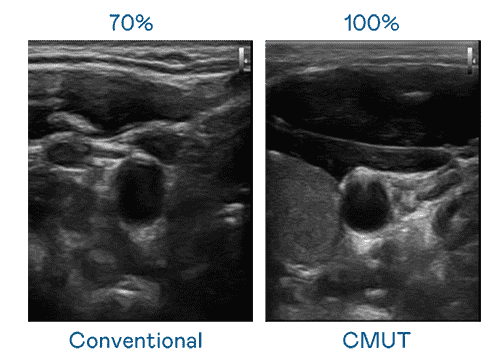

CMUT 技术是一种用电容式微机电元件来产生超音波讯号的技术。。。与传统 PZT 压电式技术相比,,,CMUT 频宽增加 30%,,更宽频的超音波讯号让影像解析度大幅提升,,是实现高影像品质医疗超音波扫描、、、、促进精准医疗发展的关键技术。。。。

大频宽带来超清晰影像

超音波影像的解析度高低,,,,首先取决于探头能发出的讯号频宽。。NG大舞台 CMUT 可提供高清晰的超音波讯号,,,,提供高频宽、、、高灵敏度、、影像纹理细节更高的超音波影像,,,,协助医护人员缩短影像判读时间及利用精准的医疗影像进行诊断。。。